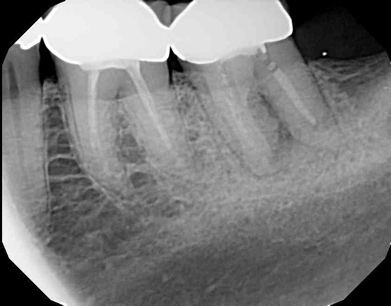

Fig 7. Cases treated by the continuous wave of condensation technique using gutta percha and epoxy resin sealer.

Fig 8. Cases treated by the continuous wave of condensation technique using gutta percha and epoxy resin sealer.

A version of warm vertical compaction, termed the continuous wave of condensation, is one of the most widely utilized obturation techniques19 (Figure 7 and Figure 8). This method involves placement of a single, tapered gutta percha cone fit to the same size as the master apical file with sealer, and downpacked with a controlled electric heat source. Based on the rotary instrumentation system used, either 04 or 06 tapered, ISO standardized apical size gutta percha cones corresponding to the final size and shape of the prepared canal can be placed with an appropriate sealer. A plugger heated to 200°F is introduced into the apical third of the root as determined by the working length to condense the apical portion of gutta percha. The heating element is turned off but left in place for an additional 5 seconds to allow slight cooling before a quick burst of heat. The heating element is removed with the coronal portion of excess gutta percha. Following this, the remainder of the canal space is filled using flowable gutta percha delivered via a motorized backfill device to the level of the chamber floor. This method can be hybridized with lateral compaction, in which spreaders are used to add accessory cones, when the shape of the canal does not allow for a tight fit of the ISO sizes of gutta percha points.

The continuous wave method of condensation, combined with gutta percha and epoxy resin sealers, covers most of Grossman's requirements for the ideal obturation of a root canal space. The deficiencies that remain, namely that gutta percha can still undergo coronal leakage, follow suit for other conventionally available materials. Given the sometimes varied nature of canal systems, it is useful to have several techniques in one's toolbox. Lateral condensation is a useful adjunctive skill to complement warm vertical methodologies when anatomy demands. That being said, it is "warm vertical or bust" for endodontists most of the time.